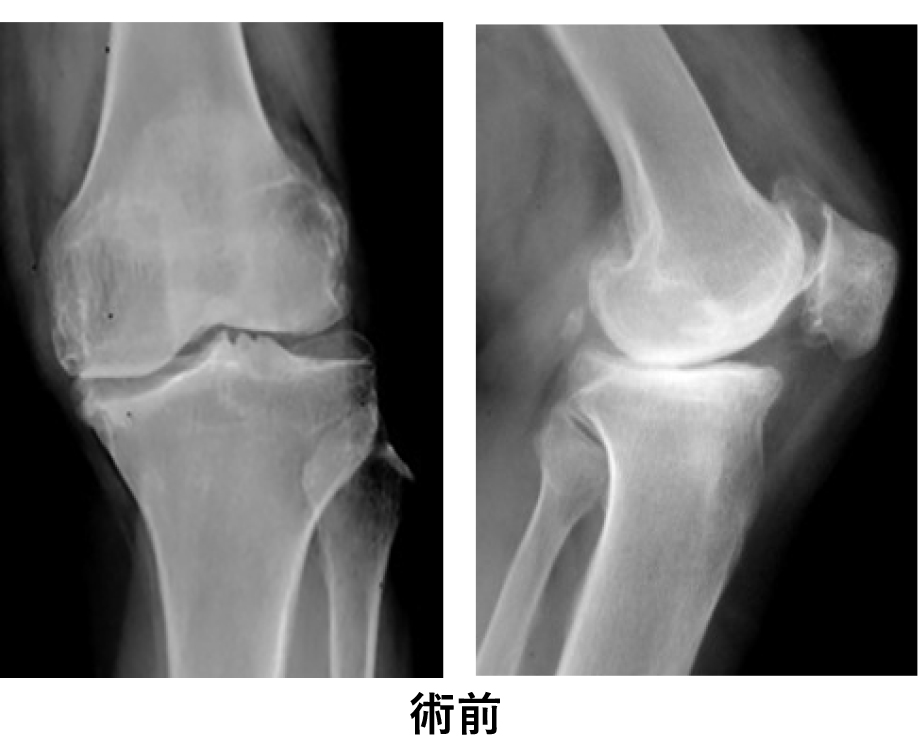

○写真で見る人工膝関節全置換術